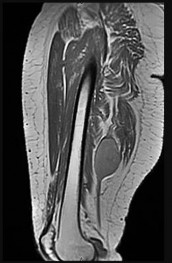

This patient has a dedifferentiated liposarcoma within a preexisting atypical lipomatous tumor. The imaging demonstrates a large fatty mass with increased internal septations proximally (the atypical lipomatous tumor) and a solid enhancing mass distally (the dedifferentiated portion). A biopsy reveals a high-grade liposarcoma. The other diagnostic responses do not reflect sarcomatous transformation of the lesion.

Surgical treatment of a high-grade sarcoma involves wide surgical resection. Radiation decreases local recurrence but does not clearly influence overall survival. The role of chemotherapy in high-grade soft-tissue sarcomas remains investigational; there is a modest (8%-15%) associated improvement in overall survival.

Intramuscular lipomas and atypical lipomatous tumors are treated with marginal resection alone. Radiation therapy for soft-tissue sarcomas may be given before or after surgery. When administered before surgery, patients have a higher wound complication rate but better long-term function attributable to lower rates of lymphedema, fibrosis, and contractures.